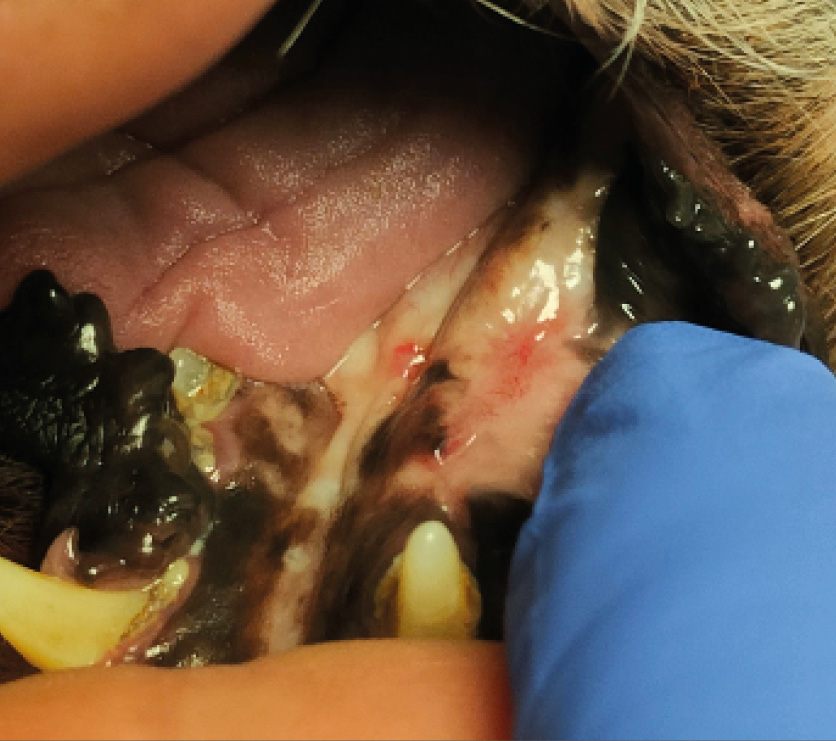

Tumores de la cavidad oral

Los tumores de la cavidad oral constituyen aproximadamente el 6–7 % de todas las neoplasias en perros y cerca del 3 % en gatos. En la especie canina, los tipos tumorales más prevalentes son el melanoma maligno, el CCE y el fibrosarcoma. En contraste, en la especie felina, el CCE representa la neoplasia oral más frecuente.

Estas neoplasias se caracterizan por un elevado grado de infiltración local, lo que condiciona un enfoque terapéutico agresivo. La cirugía y la radioterapia son consideradas las modalidades terapéuticas de elección para el control local. No obstante, en situaciones donde la intervención quirúrgica no es viable —ya sea por decisión del tutor o por limitaciones clínicas—, y cuando el acceso a la radioterapia es restringido o inexistente, la electroquimioterapia puede representar una alternativa útil para el control local del tumor (imágenes 18, 19 y 20).

En otro estudio, centrado en el tratamiento del CCE oral no tonsilar, se observó una tasa de respuesta global del 90,3 %, con un 72 % de respuestas completas y un 18,2 % de respuestas parciales. Los resultados indicaron que los tumores con un diámetro inferior a 2 cm presentaron una mejor tasa de respuesta terapéutica, lo que sugiere que el tamaño tumoral constituye un factor pronóstico relevante en esta neoplasia (imágenes 21 y 22).

La electroquimioterapia puede emplearse como tratamiento primario en neoplasias orales de pequeño tamaño que no presentan evidencia de invasión ósea. No obstante, el tratamiento de lesiones localizadas en regiones más caudales de la cavidad oral suele ser técnicamente más complejo, y en aquellos casos en los que el tumor se encuentra cerca de piezas dentales, puede ser necesaria la extracción de estas para permitir una adecuada aplicación del tratamiento. Debe tenerse particular precaución en el manejo de tumores localizados en la lengua o en la región sublingual, debido al elevado riesgo de necrosis tisular y al posible fracaso terapéutico, aspectos que deben ser claramente comunicados a los tutores de los pacientes.

Además, la electroquimioterapia puede ser utilizada con fines paliativos, especialmente en el control del sangrado asociado a tumores orales avanzados. Asimismo, su aplicación en combinación con cirugía se ha explorado como estrategia terapéutica en tumores de gran tamaño, con comportamiento infiltrativo y compromiso óseo, en los que contribuye al control local de la enfermedad.